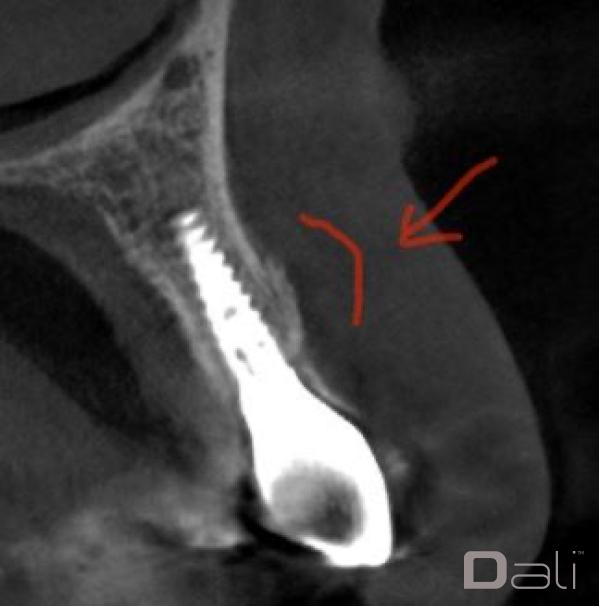

Initial Case Photos

Following a GBR at the time of implant placement, a buccal ridge deficiency persisted. Surgical uncovery of the implant to expose the cover screw revealed successful bone regeneration around the implant, but a residual lack of ridge contour. Instead of using a traditional particulate graft covered with a resorbable membrane, a “flexible bone graft” sheet, DALI Flex Graft, was placed over the buccal plate to augment the buccal contour. Because the graft comes hydrated, it is easy to handle and adapt to the defect location. The flap was then pulled over the graft and adapted around the healing abutment. Following 6 weeks of healing, we see nice healing and an obvious increase in the facial contour.